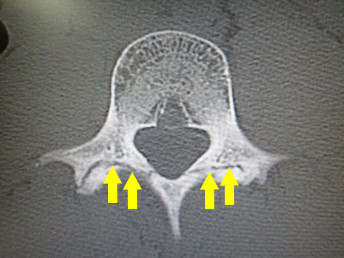

腰椎分離症のCT。突起間部の一部に骨折がみえる。